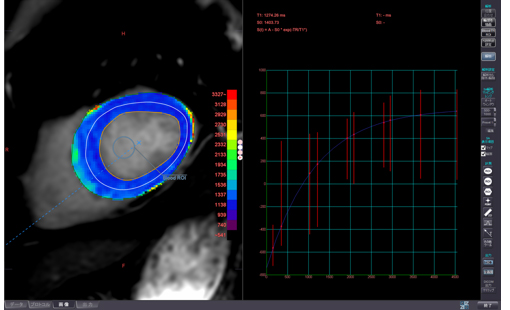

急性心筋梗塞の1例:シネMRI画像(左から中央)では、左心室の一部で収縮が低下している領域があり、心筋の浮腫(T2)画像では、同部位に信号値の高い部分を認め、急性心筋梗塞の所見となります。

左心室機能解析:心臓の機能解析が可能です。

T1 mapping:左心室の性状評価が可能です。